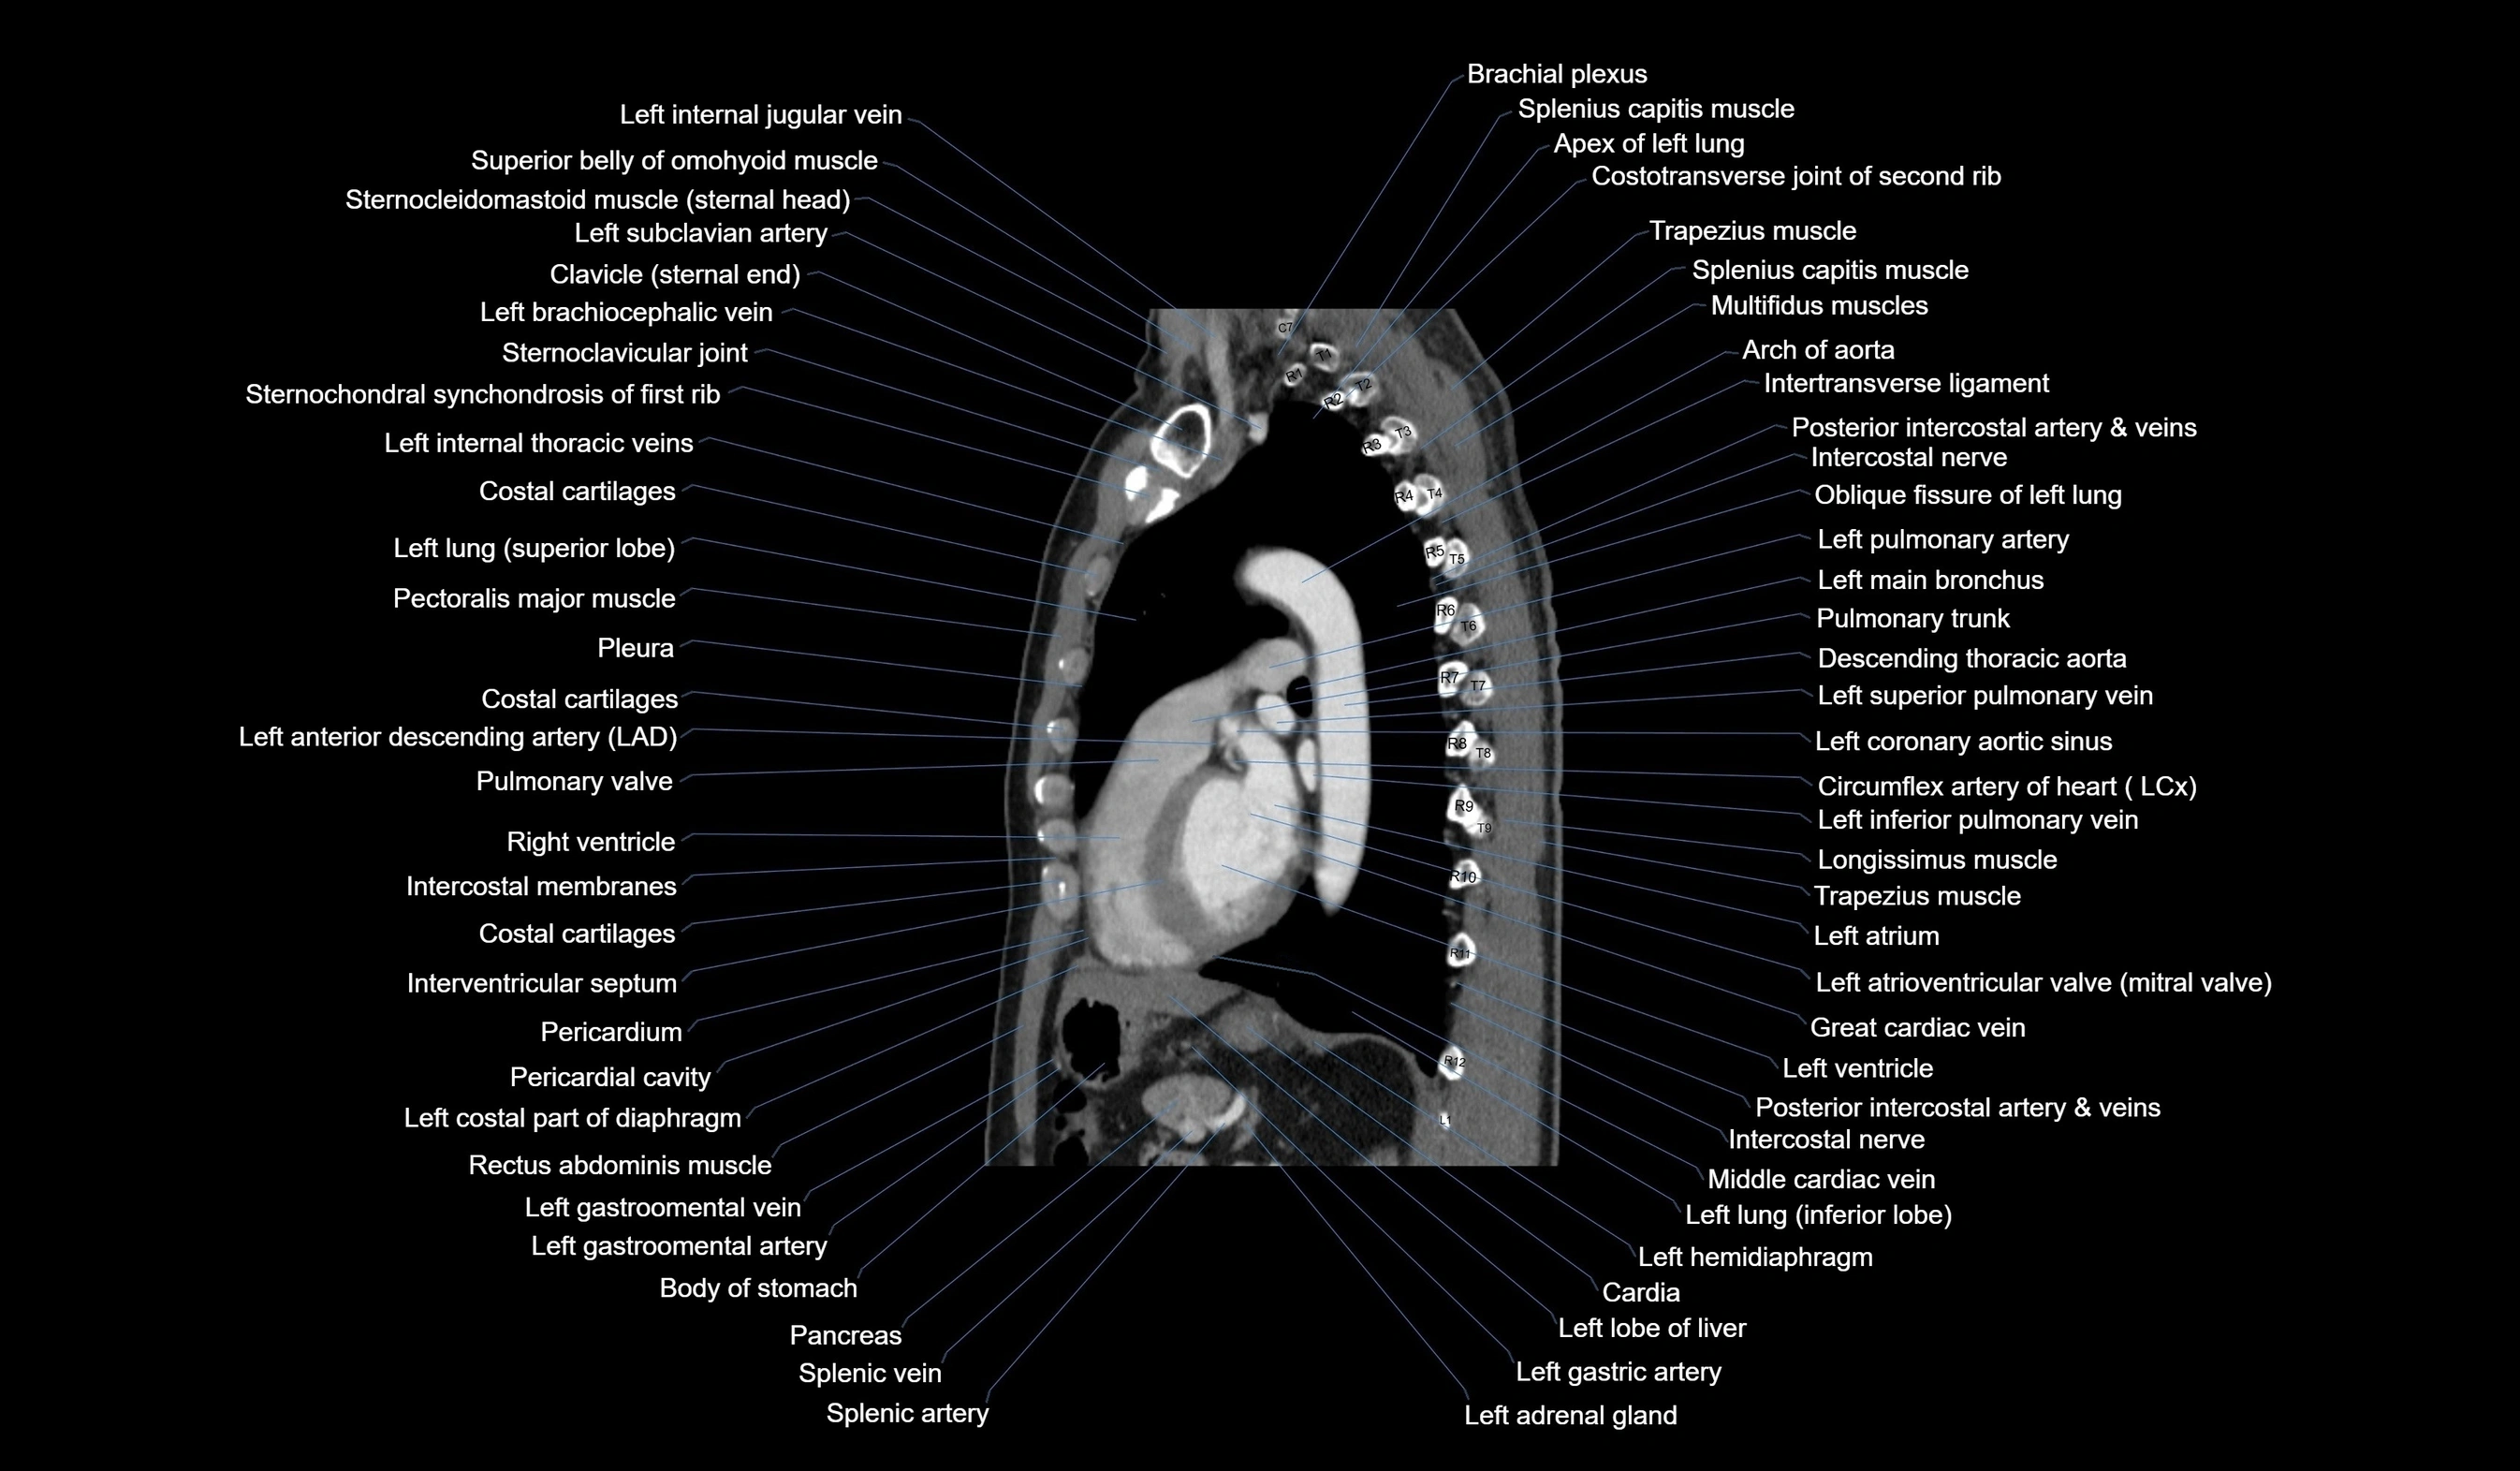

- Brachial plexus

- Left atrium

- Left ventricle

- Left main bronchus

- Left pulmonary artery

- Left superior pulmonary vein

- Left inferior pulmonary vein

- Pulmonary valve

- Left anterior descending artery (LAD)

- Descending thoracic aorta

- Arch of aorta

- Pericardium

- Pericardial cavity

- Pancreas

- Splenic artery

- Splenic vein